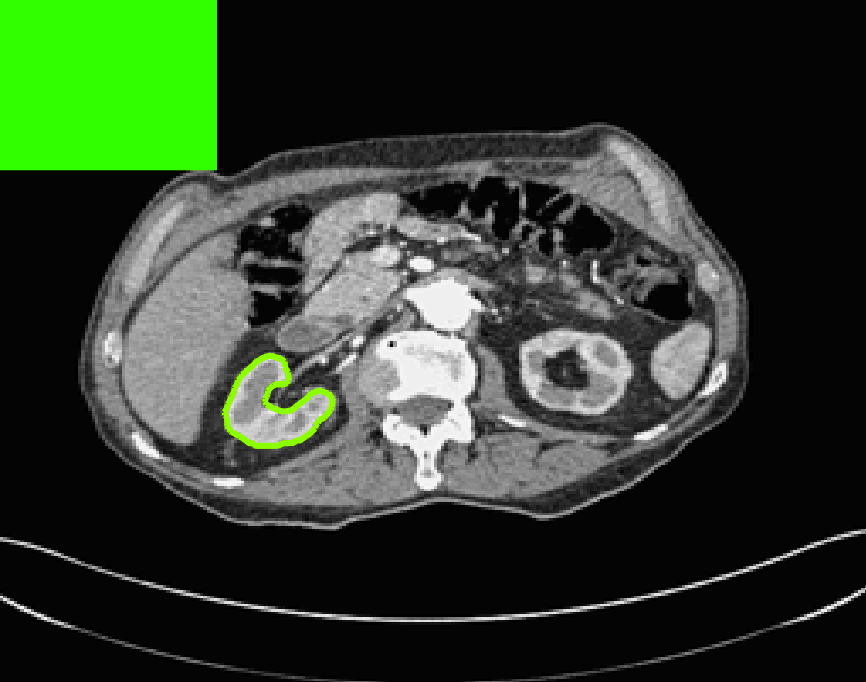

The motivation for this work comes from observing contradictions in using piecewise-constant intensity fitting terms in selective segmentation. Whilst good results are possible with this approach, the exceptional cases lead to severe limitations in practice. This is quite common in medical imaging as demonstrated in Fig. 1, where the target foreground has a low intensity. Given that the corresponding background includes large regions of low intensity, the optimal average intensities for this segmentation problem are and . For cases where , we see that by (1), almost everywhere in the domain . This means that it is very difficult to achieve an adequate result, without an over-reliance on the user input or parameter selection.

| (10) |

for and as defined in (33). This is consistent with respect to the intensities of the observed object and the concept of selective segmentation. In Fig. 3 we see the difference between CV and the proposed fitting terms for given user input on a CT image. For the CT image, the CV fitting terms are near 0 within the target region. This is despite there being a distinct homogeneous area with good contrast on the boundary. This illustrates the problem we are aiming to overcome. With the proposed fitting term this phenomenon should be avoided in cases like this. By defining as in (33) there is no contradiction if the foreground and background intensities of the target region are similar.